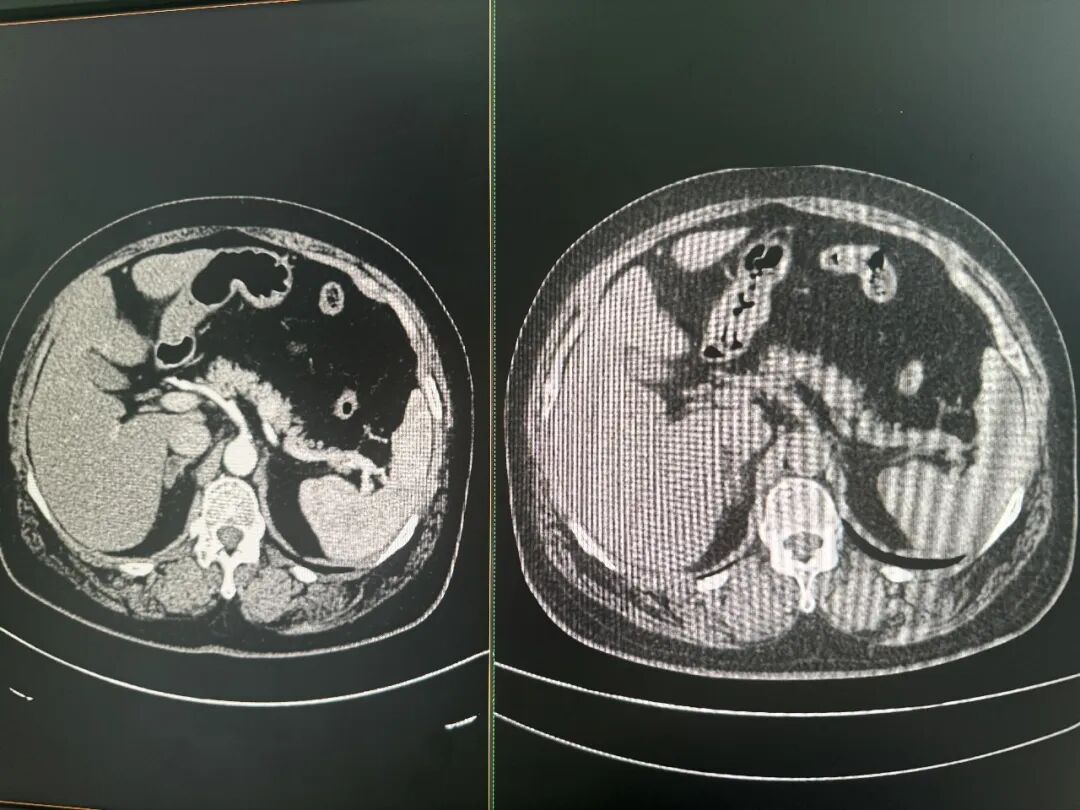

增强CT(左)和平扫CT(右)对比图 图片来源:每经记者 郑雨航 摄

达摩院医疗AI肿瘤早筛和影像智能的算法负责人张灵对每经记者解释,CT影像本质上是一串从-1024到1024的连续数值,不同数值对应不同密度的组织。许多细节超出了人眼的分辨极限,但理论上可以通过数据和算法进行分辨。